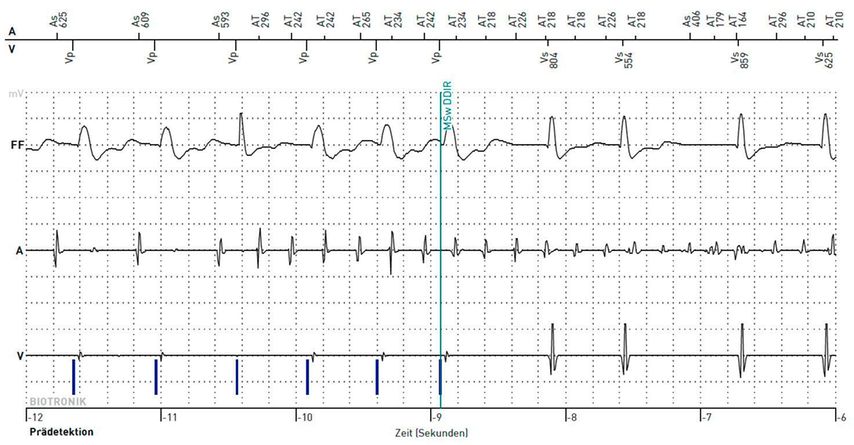

Im Unterschied zum klassischen oder klinischen VHF treten beim subklinischen keine Beschwerden auf und es wird in keinem 12-Kanal-EKG dokumentiert. Unter dem Begriff subklinisches VHF versteht man zumeist kurze, seltene atriale Rhythmusereignisse, die durch Geräte mit einer kontinuierlichen EKG-Überwachung (z.B.Loop-Rekorder, Schrittmacher und ICD mit Vorhofsonde) aufgezeichnet werden. Deshalb wird auch oft der Begriff „device“-detektiertes subklinisches VHF verwendet. Darunter werden „atrial high-rate episodes“ (AHRE) durch die ESC wie folgt definiert: „device“-detektierte atriale Tachykardien mit einer Frequenz höher als 170 Schläge pro Minute (Abb.1). Zur Diagnosesicherung müssen diese Episoden manuell durch einen Arzt analysiert werden.1,2 Die Begriffe subklinisches VHF und AHRE sind so gesehen keine Synonyme. Allerdings beschreiben sie letztendlich die gleiche Rhythmusstörung, nämlich kurze atriale Tachykardien, die als Vorhofflimmern gewertet werden.11

Abb. 1: Intrakardiale EKG-Aufzeichnung des Beginns einer AHRE mithilfe des 2-Kammer-AICD (automatischer implantierbarer Kardioverterdefibrillator)Rivacor 7 DR-T der Fa. Biotronik